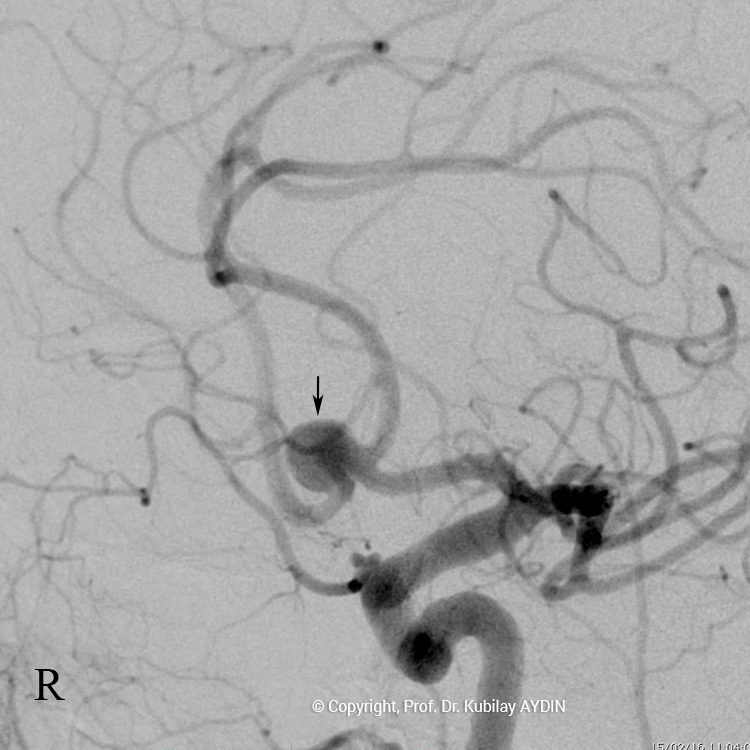

Tüm kapalı anevrizma tedavileri, hasta genel anestezi ile uyutularak gerçekleştirilir. Kapalı anevrizma tedavisinin tüm aşamaları, bacak atardamarı içine yerleştirilen 2 mm çaplı (kurşun kalemden daha ince) bir özel kateter yoluyla uygulanır. Bu küçük giriş noktasından damar içine çok ince (0.5mm çapında) ve yumuşak yapıda mikrokateter adını verdiğimiz özel plastik tüp gönderilir. Anevrizmayı kapatmak için kullandığımız bu mikrokateter, anjiografi cihazında izlenerek anevrizmanın bulunduğu damar içine yönlendirilir. İçi boş, çok ince ve yumuşak bir plastik tüp şeklinde olan mikrokateterin ucu, anevrizma kesesi içine yerleştirilir. Daha sonra bu mikrokateter içerisinden gönderilen platinden yapılmış çok yumuşak “koil” adı verilen tellerle anevrizma kesesi doldurulur. Koiller, anevrizma kesesi içinde bir yumak oluşturup, anevrizma içine kan girişini engeller. Anevrizma kesesi, koillerle tamamen doldurulup, anevrizma içine kan girişi tam olarak durduğu zaman, mikrokateter anevrizma içinden geri alınarak işlem tamamlanır. Anevrizmanın koil adı verilen özel tellerle doldurularak kapatılma işlemine, "koilleme" adı verilir. Anevrizmanın koillenerek kapatılması işlemi, oldukça güvenli ve etkili bir tedavi yöntemidir. Kanamamış beyin anevrizması olan hasta, koilleme yöntemi ile tedavi edildikten 1-2 gün sonra hasta normal günlük yaşamına dönebilir.

Anevrizma kesesinin damarla birliştiği noktasına, “anevrizmanın boynu” denir. Boynu geniş olan anevrizmaların tedavisinde, anevrizma içine konulacak koillerin, anadamar içine sarkmaması için yardımcı cihazlar kullanmak gerekebilir. Geniş boyunlu anevrizmaların koillenmesi sırasında özel yapıda balonlar veya stentler (metal kafes) kullanmak gerekebilir.